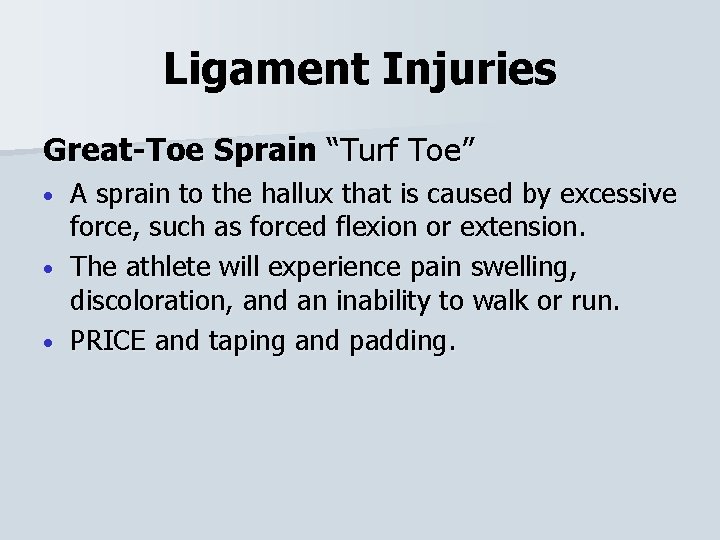

Ligament Injuries Great-Toe Sprain “Turf Toe” A sprain to the hallux that is caused by excessive force, such as forced flexion or extension. • The athlete will experience pain swelling, discoloration, and an inability to walk or run. • PRICE and taping and padding. •